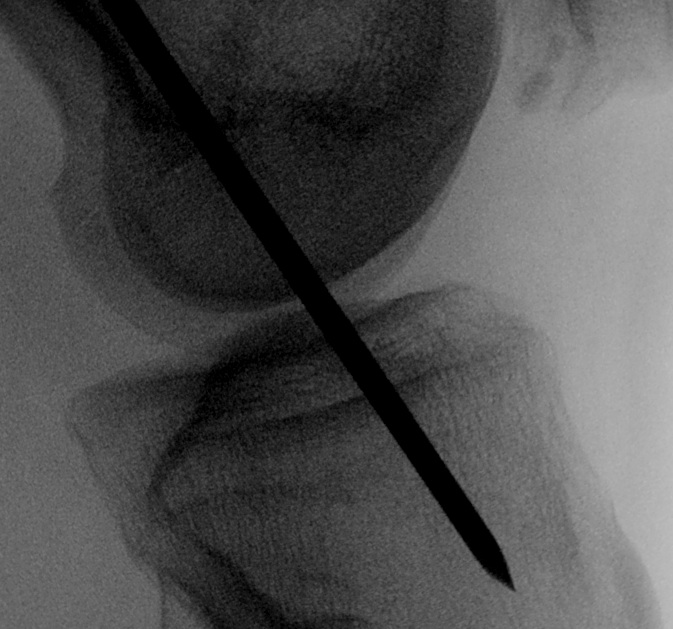

Tibial entry point

- extend knee

- aim pin for standard origin of ACL

- drive through tibia

Ream tibial and femoral tunnels

- line to line to graft size

- outside in to preserve native ACL